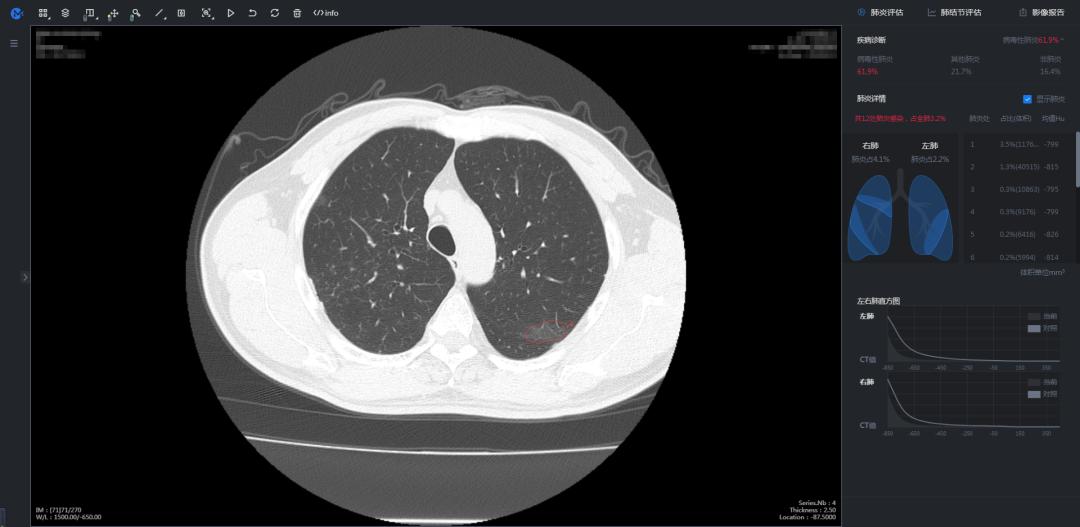

腾讯AI诊断输出图

投入使用后,医护人员给的反馈都非常理想,因为阅片不用那么累了。当时医生阅读、分析CT影像的压力非常大,临床诊断标准改变以后,每日新增确诊病例暴涨将近十倍,每位患者做一次胸部CT,会产生300张影像,每次医生肉眼阅片要耗费5-15分钟。

AI最快两秒钟就能判断出这个人是否得了肺炎,他得的肺炎是不是新冠肺炎。如果AI判断这个人是新冠肺炎,它还会在CT影像中圈出标示出病灶,告诉医生它判断的依据,标示的过程最多需要一分钟。

AI的判断不能直接作为医疗诊断的依据,但是可以为医生提供参考,大大提高了诊断效率。